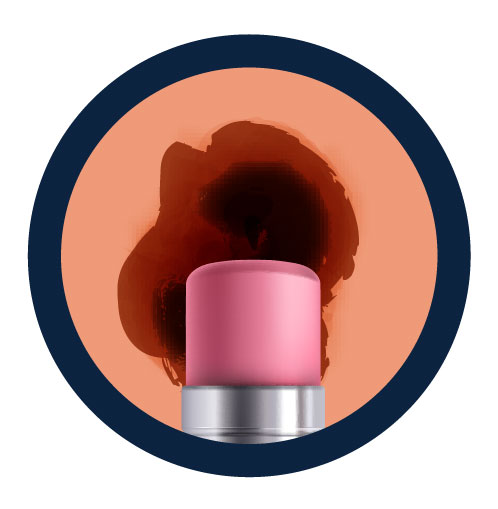

Use sunscreen

For extended outdoor activity, use a water-resistant, broad spectrum sunscreen with an SPF of 30 or higher.